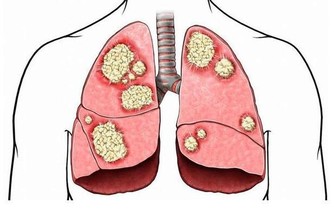

抑制癌症

維生素e對於多種癌症的一直抵抗作用都是具有明顯作用的。特別是維生素e對於腫瘤細胞的分化作用進行阻止是不可逆轉的,正是維生素e對於腫瘤細胞分化的阻止作用能夠有效抑制腫瘤細胞的不斷分解擴散,抑制癌症。